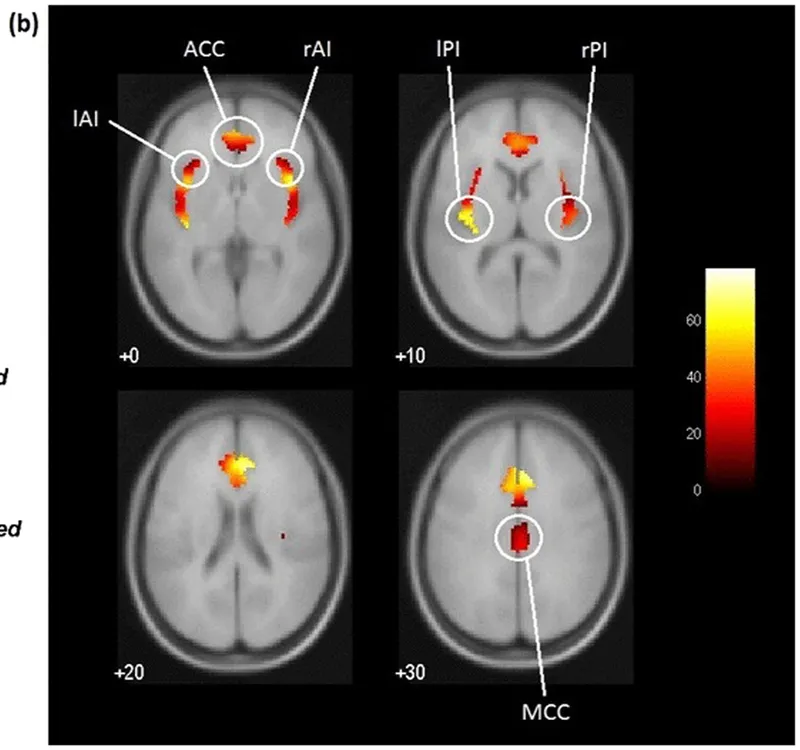

• The brain's pain-empathy network encodes outcome severity and drives blame, but is recruited differently for acceptability judgments – a neural dissociation between two outwardly similar moral responses

• Individuals who incur costly personal sacrifices to rescue others in a virtual emergency have larger right anterior insula – a region central to empathic motivation